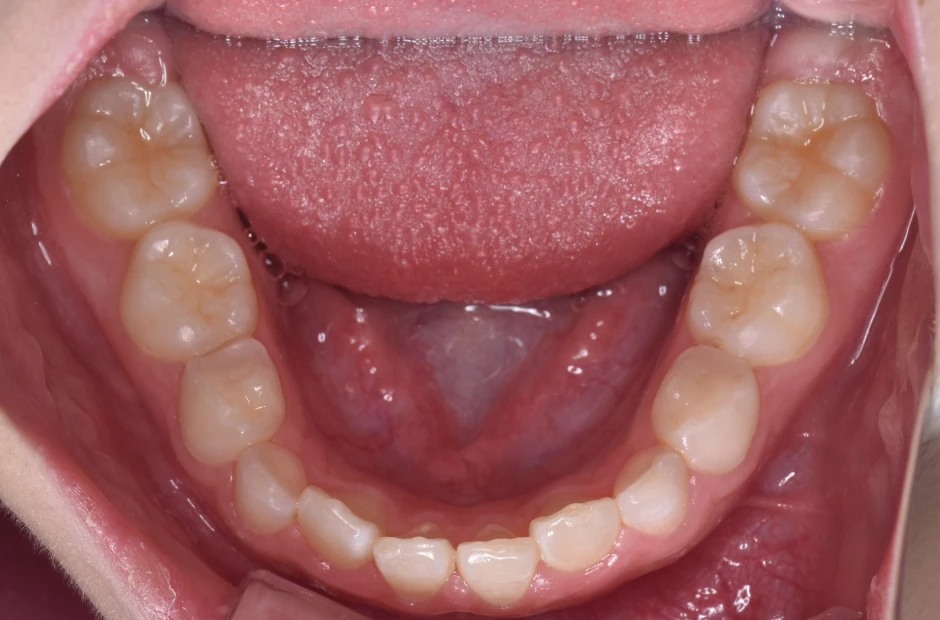

前歯部反対咬合とすきっ歯

| 診断名・主訴 | 前歯部反対咬合とすきっ歯 |

|---|---|

| 年齢・性別 | 7歳・女性 |

| 治療期間・回数 | 1年半、月一回 |

| 治療に用いた主な装置 | 床拡大装置+ブラケット(前歯部) |

| 抜歯部位 | なし |

| 治療費 | 30万円(税抜) |

| リスク・副作用 | 装置による違和感・疼痛・歯肉退縮・歯根吸収・虫歯のリスクなど |

治療前

治療後